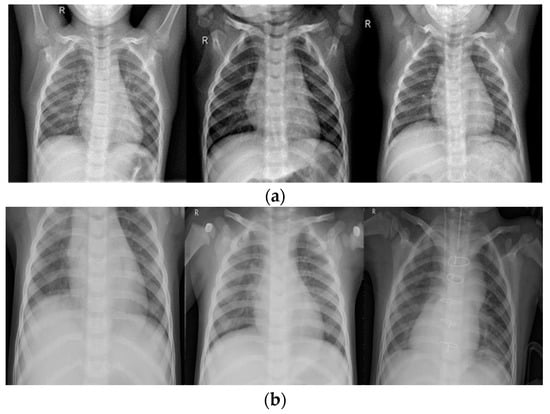

Figure 2 provides several examples between the original and enhanced images. Figure 2a represents examples from original data set, while Figure 2b represents examples from the enhanced data set. As shown, the upper images always contain gray and vague areas while lower images display almost white and black areas, showing that the enhancement technique plays a significant role in image contrast. In this study, the information implicit in original images, like bones, lung areas, and other tissues, is revealed by the DHE technique.

Figure 2.

Comparison of original and enhanced images. (a) Examples of original images; (b) examples of enhanced images.